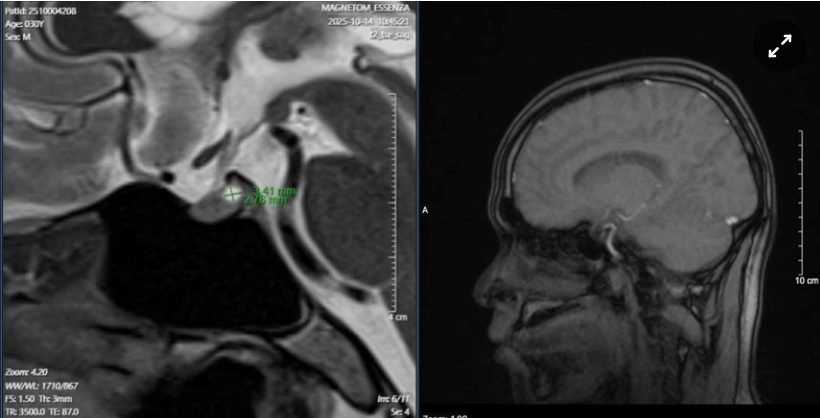

Để tìm nguyên nhân, các bác sĩ chỉ định chụp MRI sọ não, kết quả phát hiện anh T. có u tuyến yên - một khối u lành tính nằm ở đáy não, có thể ảnh hưởng đến toàn bộ hệ thống nội tiết.

Hình ảnh khối y tuyến yên của bệnh nhân N.V.T.. Ảnh: BSCC.